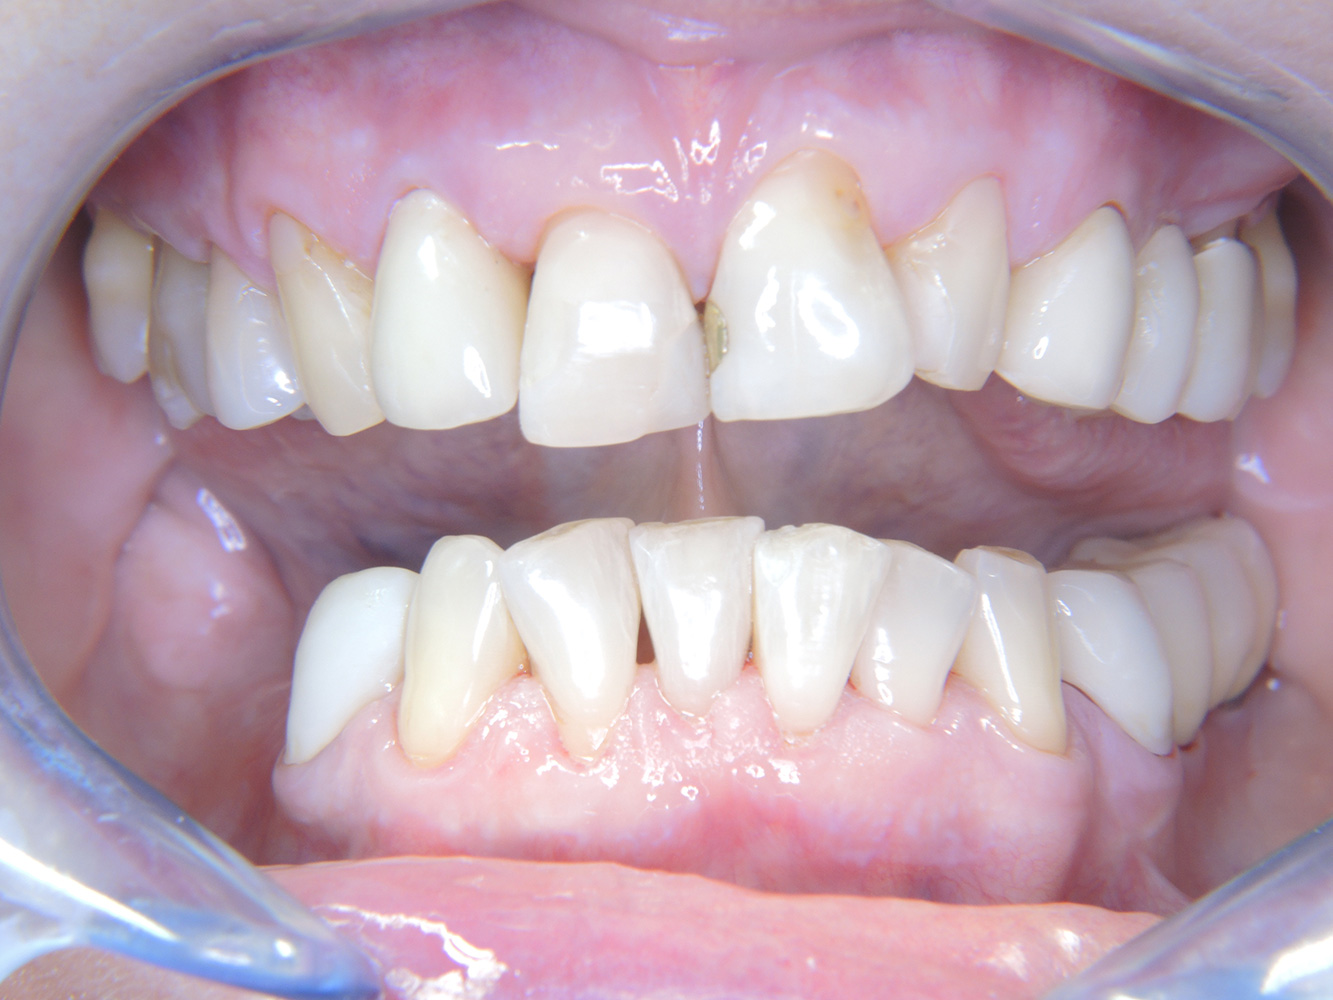

La paziente sana con precedente patologia parodontale*

Questa paziente di 68 anni non presenta alcuna patologia precedente né segue alcuna terapia che possano ritenersi rilevanti dal punto di vista odontoiatrico, e il suo stile di vita non comporta alcun rischio particolare. La paziente ha due impianti (3° quadrante, da cinque anni) e una precedente patologia parodontale (parodontite allo stadio IV, grado B) con perdita del dente. Al momento le condizioni parodontali sono stabili, tuttavia la parodontite aumenta in misura significativa le complicazioni biologiche degli impianti e c'è dunque il rischio di perdita dell'impianto (21). Per la seduta di profilassi si possono formulare quattro consigli.